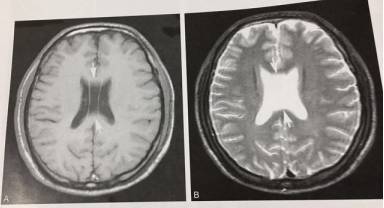

4、第五脑室(透明隔间腔)

T1WI及T2WI显示双侧侧脑室体部间槽状脑脊液信号影,边界清晰。

5、第六脑室

T1WI及T2WI显示透明隔后方不规则囊状灶,与脑脊液信号一致,边界清楚。